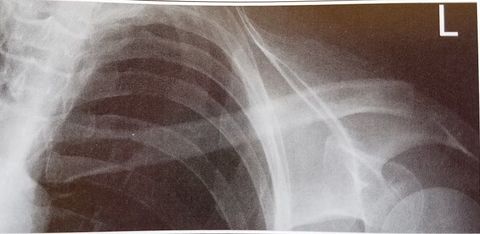

| PA Oblique Scapular Y-Lateral | Excessive Obliquity |

| PA Oblique Scapular Y-Lateral | Insufficient Obliquity |

| PA Oblique Scapular Y-Lateral | MCP is tilted anteriorly |

| PA Oblique Scapular Y-Lateral | MCP is tilted posteriorly |

| Scapular Y-Lateral | ANATOMY: humeral head resting in the 'Y' of the acromion and coracoid process CRITERIA: vertebral border and lateral border of scapula are directly superimposed humeral head is aligned with body of scapula POSITIONING: pt's unaffected arm is abducted 90 degrees, pt in 45-60 degree anterior oblique CR perpendicular @ scapulohumeral joint (neer) CR angled 10-15 degrees caudal @ scapulohumeral joint |